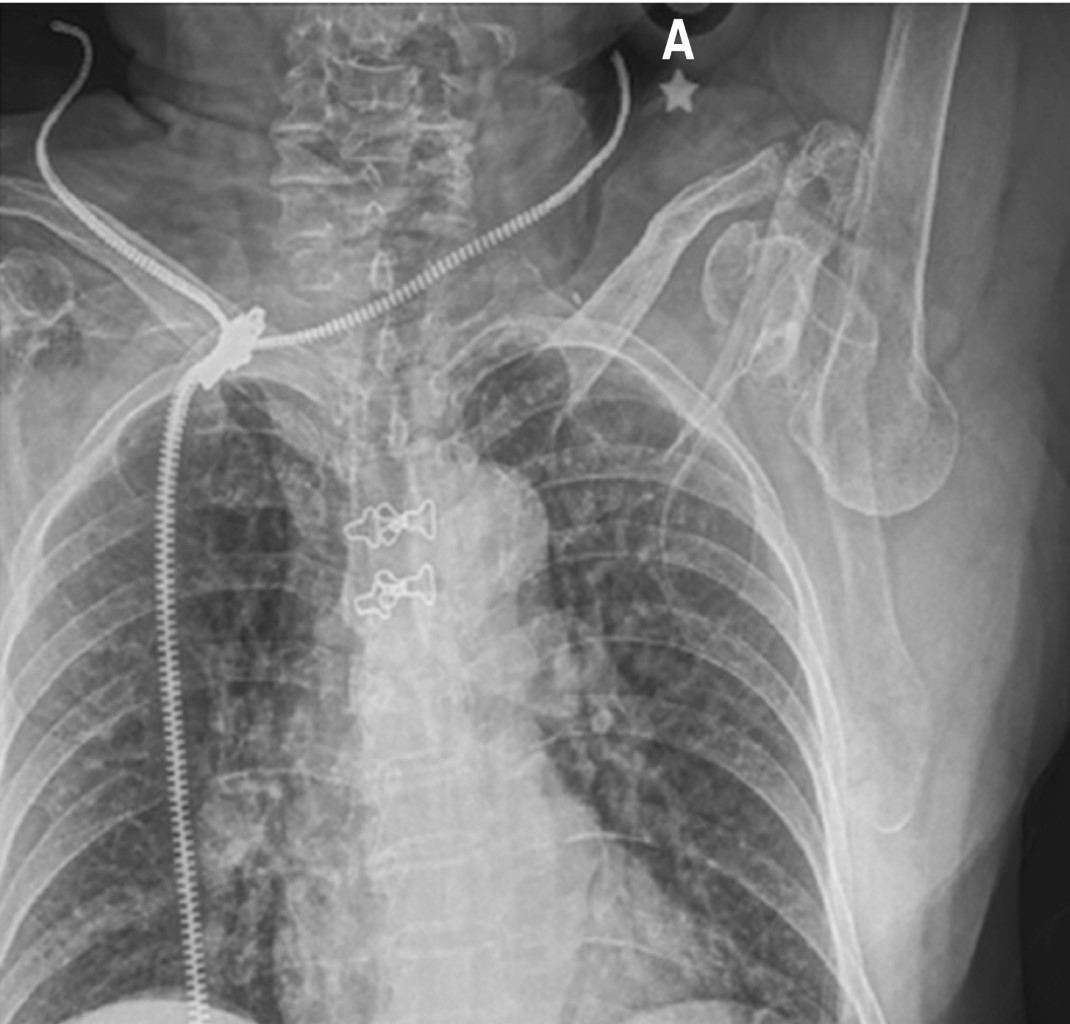

Paciente femenino de 86 años es traída al servicio de urgencias tras caída desde su propio plano de sustentación. El motivo de consulta era dolor en hombro izquierdo y codo ipsilateral. En la exploración física se observaba deformidad en codo y a paciente con miembro torácico por encima de la cabeza, siendo sostenido por extremidad contralateral para disminuir el dolor. La extremidad torácica izquierda se encontraba en abducción máxima y la paciente no era capaz de aducir el hombro. La cabeza humeral era palpable en el borde inferior de la axila. A la exploración neurovascular no se encontraron datos que sugirieran lesión. Radiografías de codo y hombro en proyección anteroposterior y lateral mostraron luxación inferior del hombro (Figuras 1 y 2), así como luxación posterior del codo sin lesión ósea asociada. Ambas lesiones fueron manejadas en quirófano mediante reducción cerrada con paciente bajo sedación. La luxación inferior del hombro fue reducida mediante tracción-contra-tracción del húmero con posterior aducción del hombro. La articulación del codo fue reducida mediante tracción axial con la muñeca en supinación con posterior flexión. Se realizó exploración neurovascular al término donde no se observaron lesiones. Se obtuvieron radiografías de control que evidenciaron correcta localización de la articulación del codo (Figuras 3 y 4) así como de la cabeza humeral (Figura 5). Debido a la mejoría, la paciente fue egresada con férula a 90o e inmovilizador de hombro, iniciando rehabilitación a las 2.5 semanas con movimientos pasivos pendulares de hombro y movimientos de flexión y extensión de codo. El seguimiento se da en la consulta externa a las cuatro semanas, tres y seis meses evolucionando de manera favorable con reincorporación completa a sus actividades de la vida diaria.

Figura 1

Figura 2